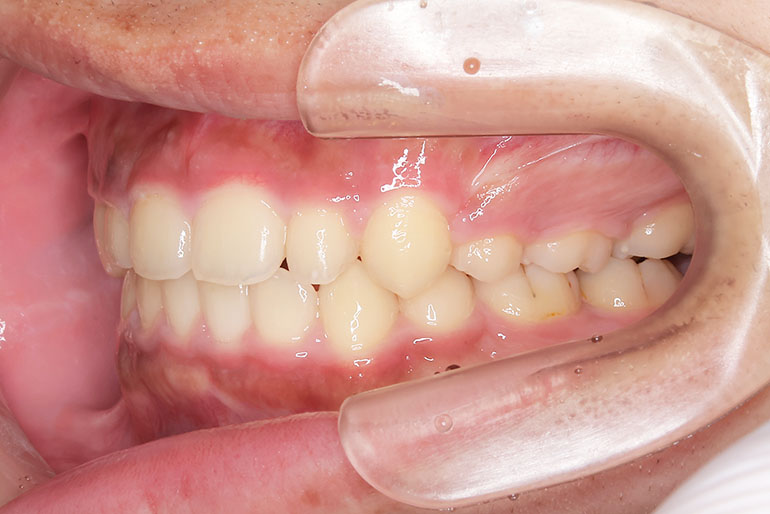

右上の前歯が生えてこない事を気にされ来院されました。 レントゲン写真から、上顎正中に過剰歯が埋伏していることが原因でしたので、抜歯して経過観察。 遅れて、無事に生えてきました。 もし、自然に生えてこない場合は、開窓して、引っぱり出します。(廷出) 状態により、引っぱり出せない場合もあります。 将来的にスペース不足により、上下顎前臼歯部に重度の叢生(がたつき)が予測できますので、がたつきを減らすために、小児矯正で側方拡大を行いました。 小児矯正で側方拡大を行ってもスペースが足りない場合(著しくスペース不足の場合)は、がたつき(叢生、八重歯)が残ります。 残ったがたつき(叢生)は、本格矯正ですべて生え変わった中学生から治せば問題ありません。 来院間隔が平均で1.5カ月でしたので半年ほど治療期間が長いです。